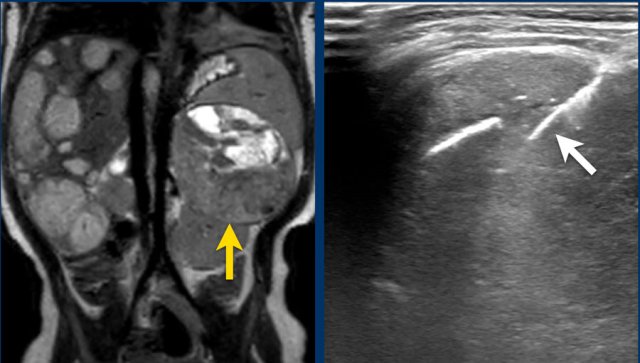

The MRI is of a nine-months-old girl with a tumor in the left abdomen. The MRI shows a tumor of the left adrenal gland, partially solid, partially cystic. Multiple liver metastases are present.

The tumor was biopsied. There was constant blood loss through the guiding needle. At the end of the procedure two gelatin foam plugs were placed (echogenic stripes (arrows).